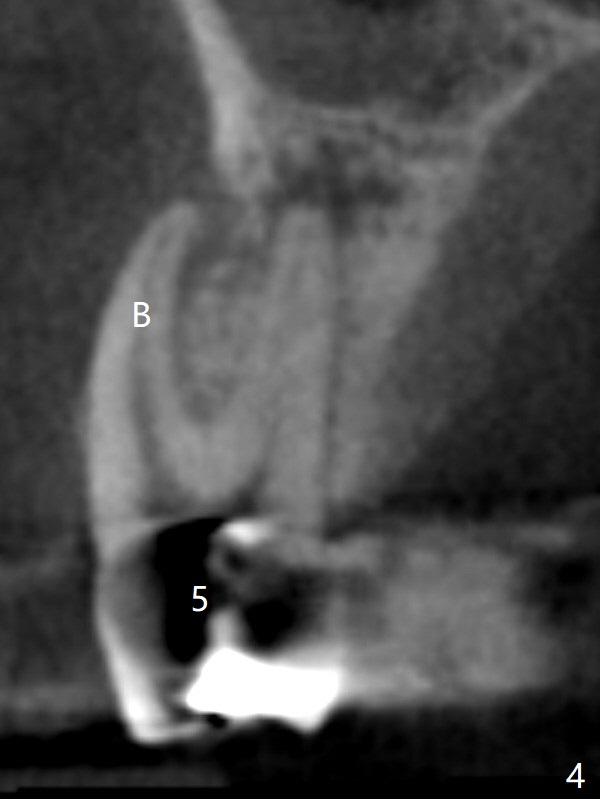

A 64-year-old man requests implant restoration after the upper FPD dislodges (Fig.1). The measurement of the septal height at #2 by PA (Fig.2) is not as precise as CBCT (Fig.11, taken 4 years earlier). There appears to be 2.8 mm bone apical to the tooth #4 (Fig.2); in contrast, the bone is more or less buccal and palatal to the root apex shown by CT (Fig.5). Furthermore CT more clearly shows apical lesions of the tooth #5 (Fig.3,4) than PA (Fig.2). In addition to pulpal test, RCT should be done for #5 prior to implant placement at #4.